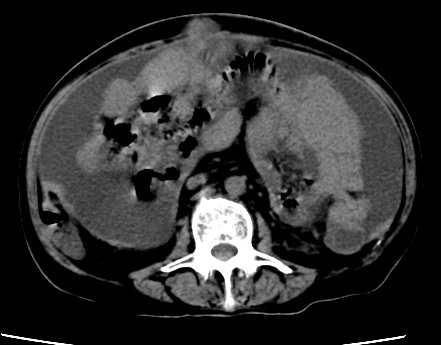

标题: CT23975:女61岁,腹部不适,明显消瘦 [打印本页]

标题: CT23975:女61岁,腹部不适,明显消瘦

既往5年前卵巢癌行子宫及附件切除,右乳癌术后一年,考虑腹膜转移?

大量腹水,考虑腹膜转移。肝脏低密度灶。1囊肿,2转移。

1)结合病史,考虑腹膜及网膜转移瘤。2)肝脏多发性低密度灶,不排除转移瘤。3)大量腹水。

考虑卵巢癌行子宫术后复发,并肝、腹腔 、大网膜转移可能性大。

大量腹水。